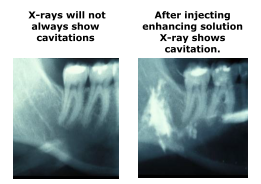

X-rays are our state of art

though they can not tell disease apart

I dream that someday testing will show

that infection doesn’t have to glow

Look again at that apex

that X-ray is actually playing tricks

Can you believe for a hundred years

That X-rays show not what appears

We’ve been told that black’s infection

and never thought of actual connections

That bone dissolves during immune protection

and “healthy” looking roots are full of infection